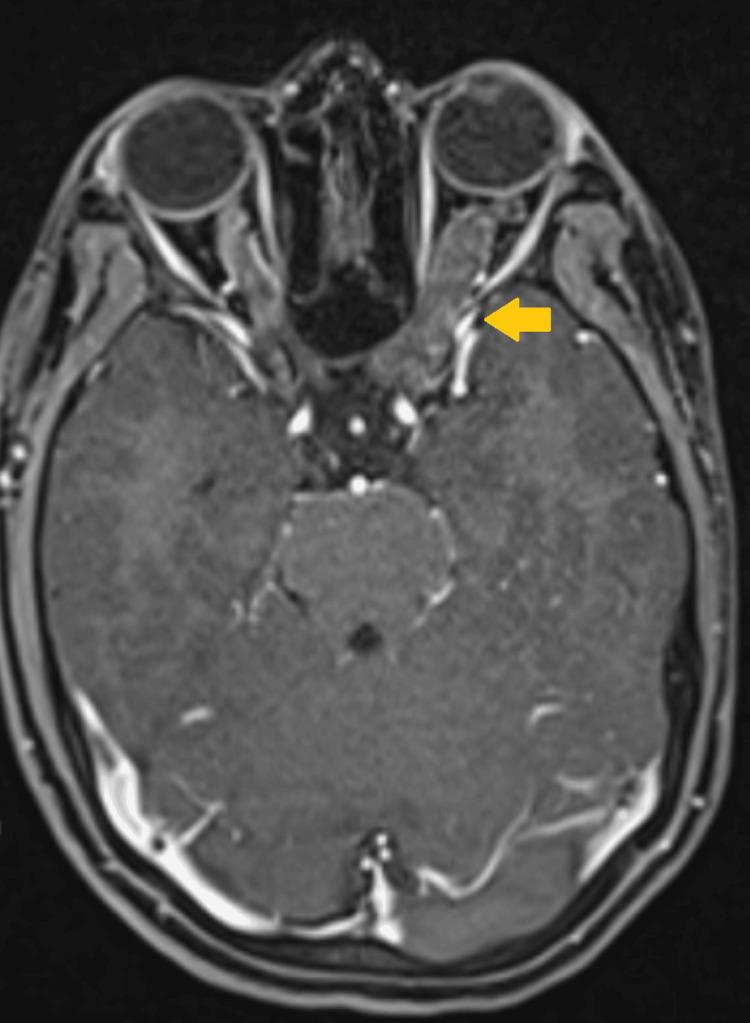

Radiotherapy offers a favorable long-term outcome for the treatment of optic pathway glioma, but at a cost of neurocognitive impairment and decreased quality of life. This has led to a chemotherapy-first approach, deferring radiotherapy till disease progression. We present a case report wherein a 20-year-old female patient with left optic nerve glioma was treated with definitive radiotherapy using a self-shielding gyroscopic radiosurgery (GRS) system. We report the first published use of GRS in the treatment of optic nerve glioma. The patient was treated with 15 Gy at the 56% isodose line in two fractions on alternate days with 17 isocenters and 271 non-coplanar beams, amounting to a total treatment time of 63 minutes. The evaluation of the treatment plan shows considerable sparing of the normal structures, which may translate into better long-term clinical outcomes. A clinical follow-up after a month of treatment showed good clinical control without any undue treatment-related toxicity. Further follow-up is slated as per standard protocol. This case report opens up the potential for considering GRS after careful scrutiny as a first-line approach in the treatment of optic nerve glioma.

放射治疗对视神经胶质瘤的治疗具有良好的长期效果,但代价是神经认知功能损害和生活质量下降。这导致了一种先进行化疗的方法,将放射治疗推迟到疾病进展时。我们报告一例病例,一名20岁患有左侧视神经胶质瘤的女性患者使用自屏蔽陀螺式放射外科手术(GRS)系统进行了根治性放射治疗。我们报告了GRS首次用于治疗视神经胶质瘤的情况。患者在56%等剂量线处以15 Gy分两次隔日给予治疗,共17个等中心和271条非共面射束,总治疗时间为63分钟。治疗计划评估显示正常结构得到了相当程度的保护,这可能转化为更好的长期临床结果。治疗一个月后的临床随访显示临床控制良好,无任何过度的治疗相关毒性。将按照标准方案进行进一步随访。本病例报告表明,经过仔细审查后,GRS有可能作为视神经胶质瘤治疗的一线方法。